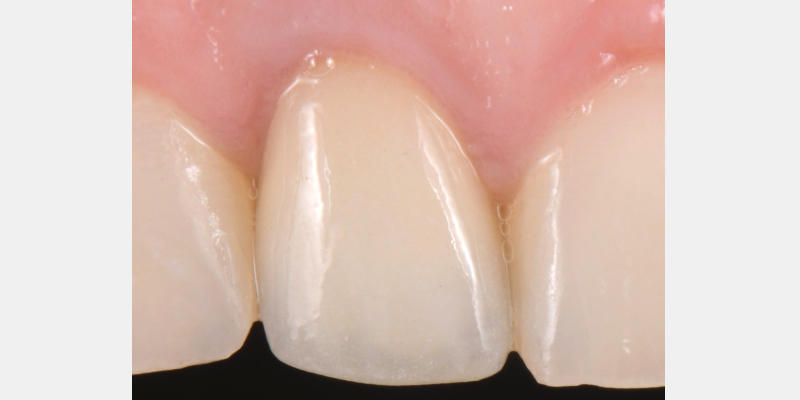

Silicone Jig Technique for Cement-Retained Implant Supported Restoration

One of the most common complications with cement-retained implant restorations is inflammation around the crown. Excess cement can lead to peri-implant diseases such as peri-implant mucositis and even bone loss. A key factor to understand is the biological difference between teeth and implants — particularly the structure of the junctional epithelium and connective tissue — which makes removing residual cement around the restoration more difficult.

Here is a simple, step-by-step technique for fabricating a silicone jig to avoid excess cement in a cement-retained implant-supported restoration. It can be applied to a single crown or to an implant-supported cement-retained bridge.